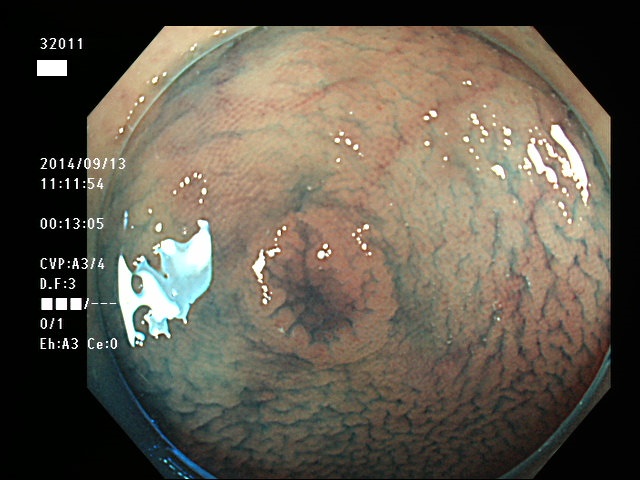

上記100名より抽出した平坦・陥凹型腺腫(=癌化の危険が高いが見落としやすい病変)の内視鏡写真